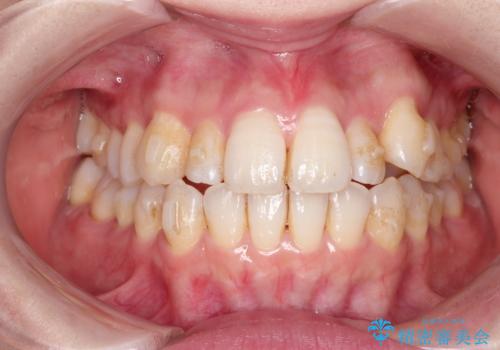

インビザラインで八重歯の矯正

- 八重歯を治したいとのことで、来院されました。

インビザラインにて、上顎の歯と歯の間をわずかに削り、並べる計画としました。